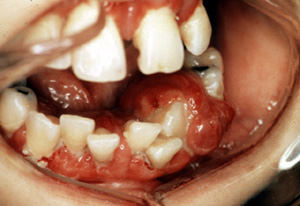

Éste es un

granuloma piógeno raro, hay considerable tejidonecrótico y exudado superficial. Tres semanas de crecimiento

rápido y la apariencia clínica parecen ominosa, pero estas lesiones

son generalmente inocuas.